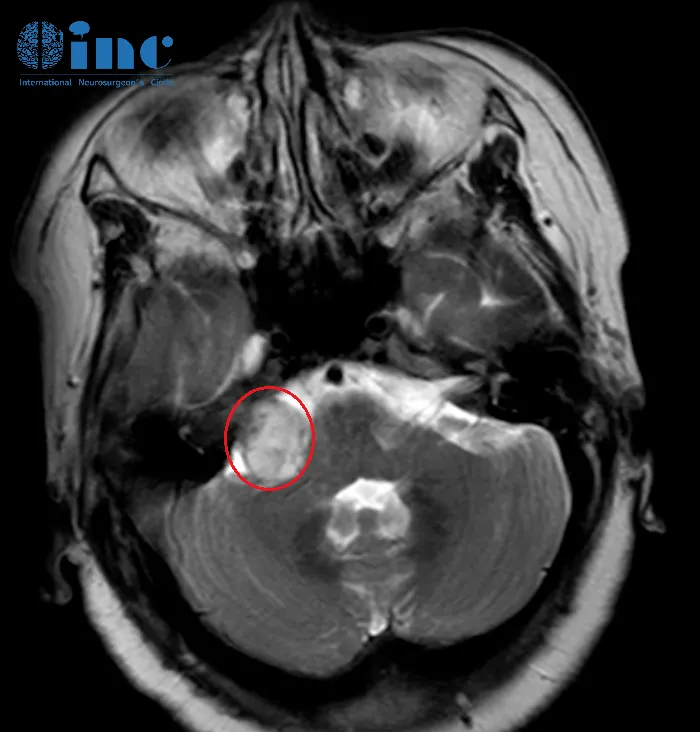

2021年,经两次MRI检查,齐奶奶最终确诊:右侧听神经瘤(20mm×15mm×19mm)合并脑积水。

2021年11月,齐奶奶先接受了脑积水引流手术,症状大为缓解。然而,2022年10月的复查带来坏消息:肿瘤已长到3厘米以上!手术迫在眉睫。